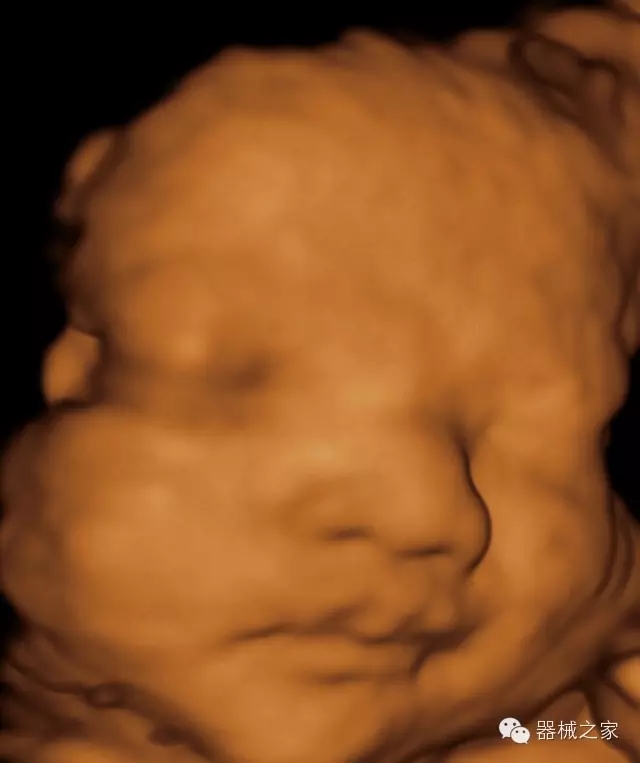

品牌:飛依諾(VINNO)

飛依諾科技(蘇州)有限公司2010年在蘇州工業(yè)園區(qū)成立,公司致力于成為世界一流醫(yī)療超聲品牌。核心創(chuàng)始團(tuán)隊(duì)囊括了來(lái)自于全球著名公司十多位資深研發(fā)和市場(chǎng)人才,均為業(yè)界精英。

經(jīng)典產(chǎn)品:VINNO 6

臨床圖片賞析

·完整的3D/4D臨床應(yīng)用,STIC, MCUT 和Auto NT等滿足產(chǎn)科所有應(yīng)用;